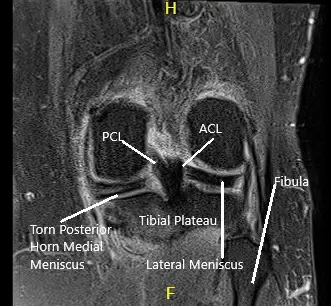

Una resonancia magnética de la rodilla izquierda sugirió osteoartrosis con pérdida de cartílago de alto grado en el compartimento medial y pérdida de cartílago de alto grado cartílago trocleare central con pérdida condral de bajo grado cartílago rotuliano. Gran desgarro radial del cuerno posterior del menisco medial , que está extruido periféricamente. Hay un cuerpo suelto en la parte profunda de la almohadilla grasa de Hoffa que mide 4 mm x 8 mm.

Resonancia magnética de la rodilla izquierda que muestra secciones axial y coronal.